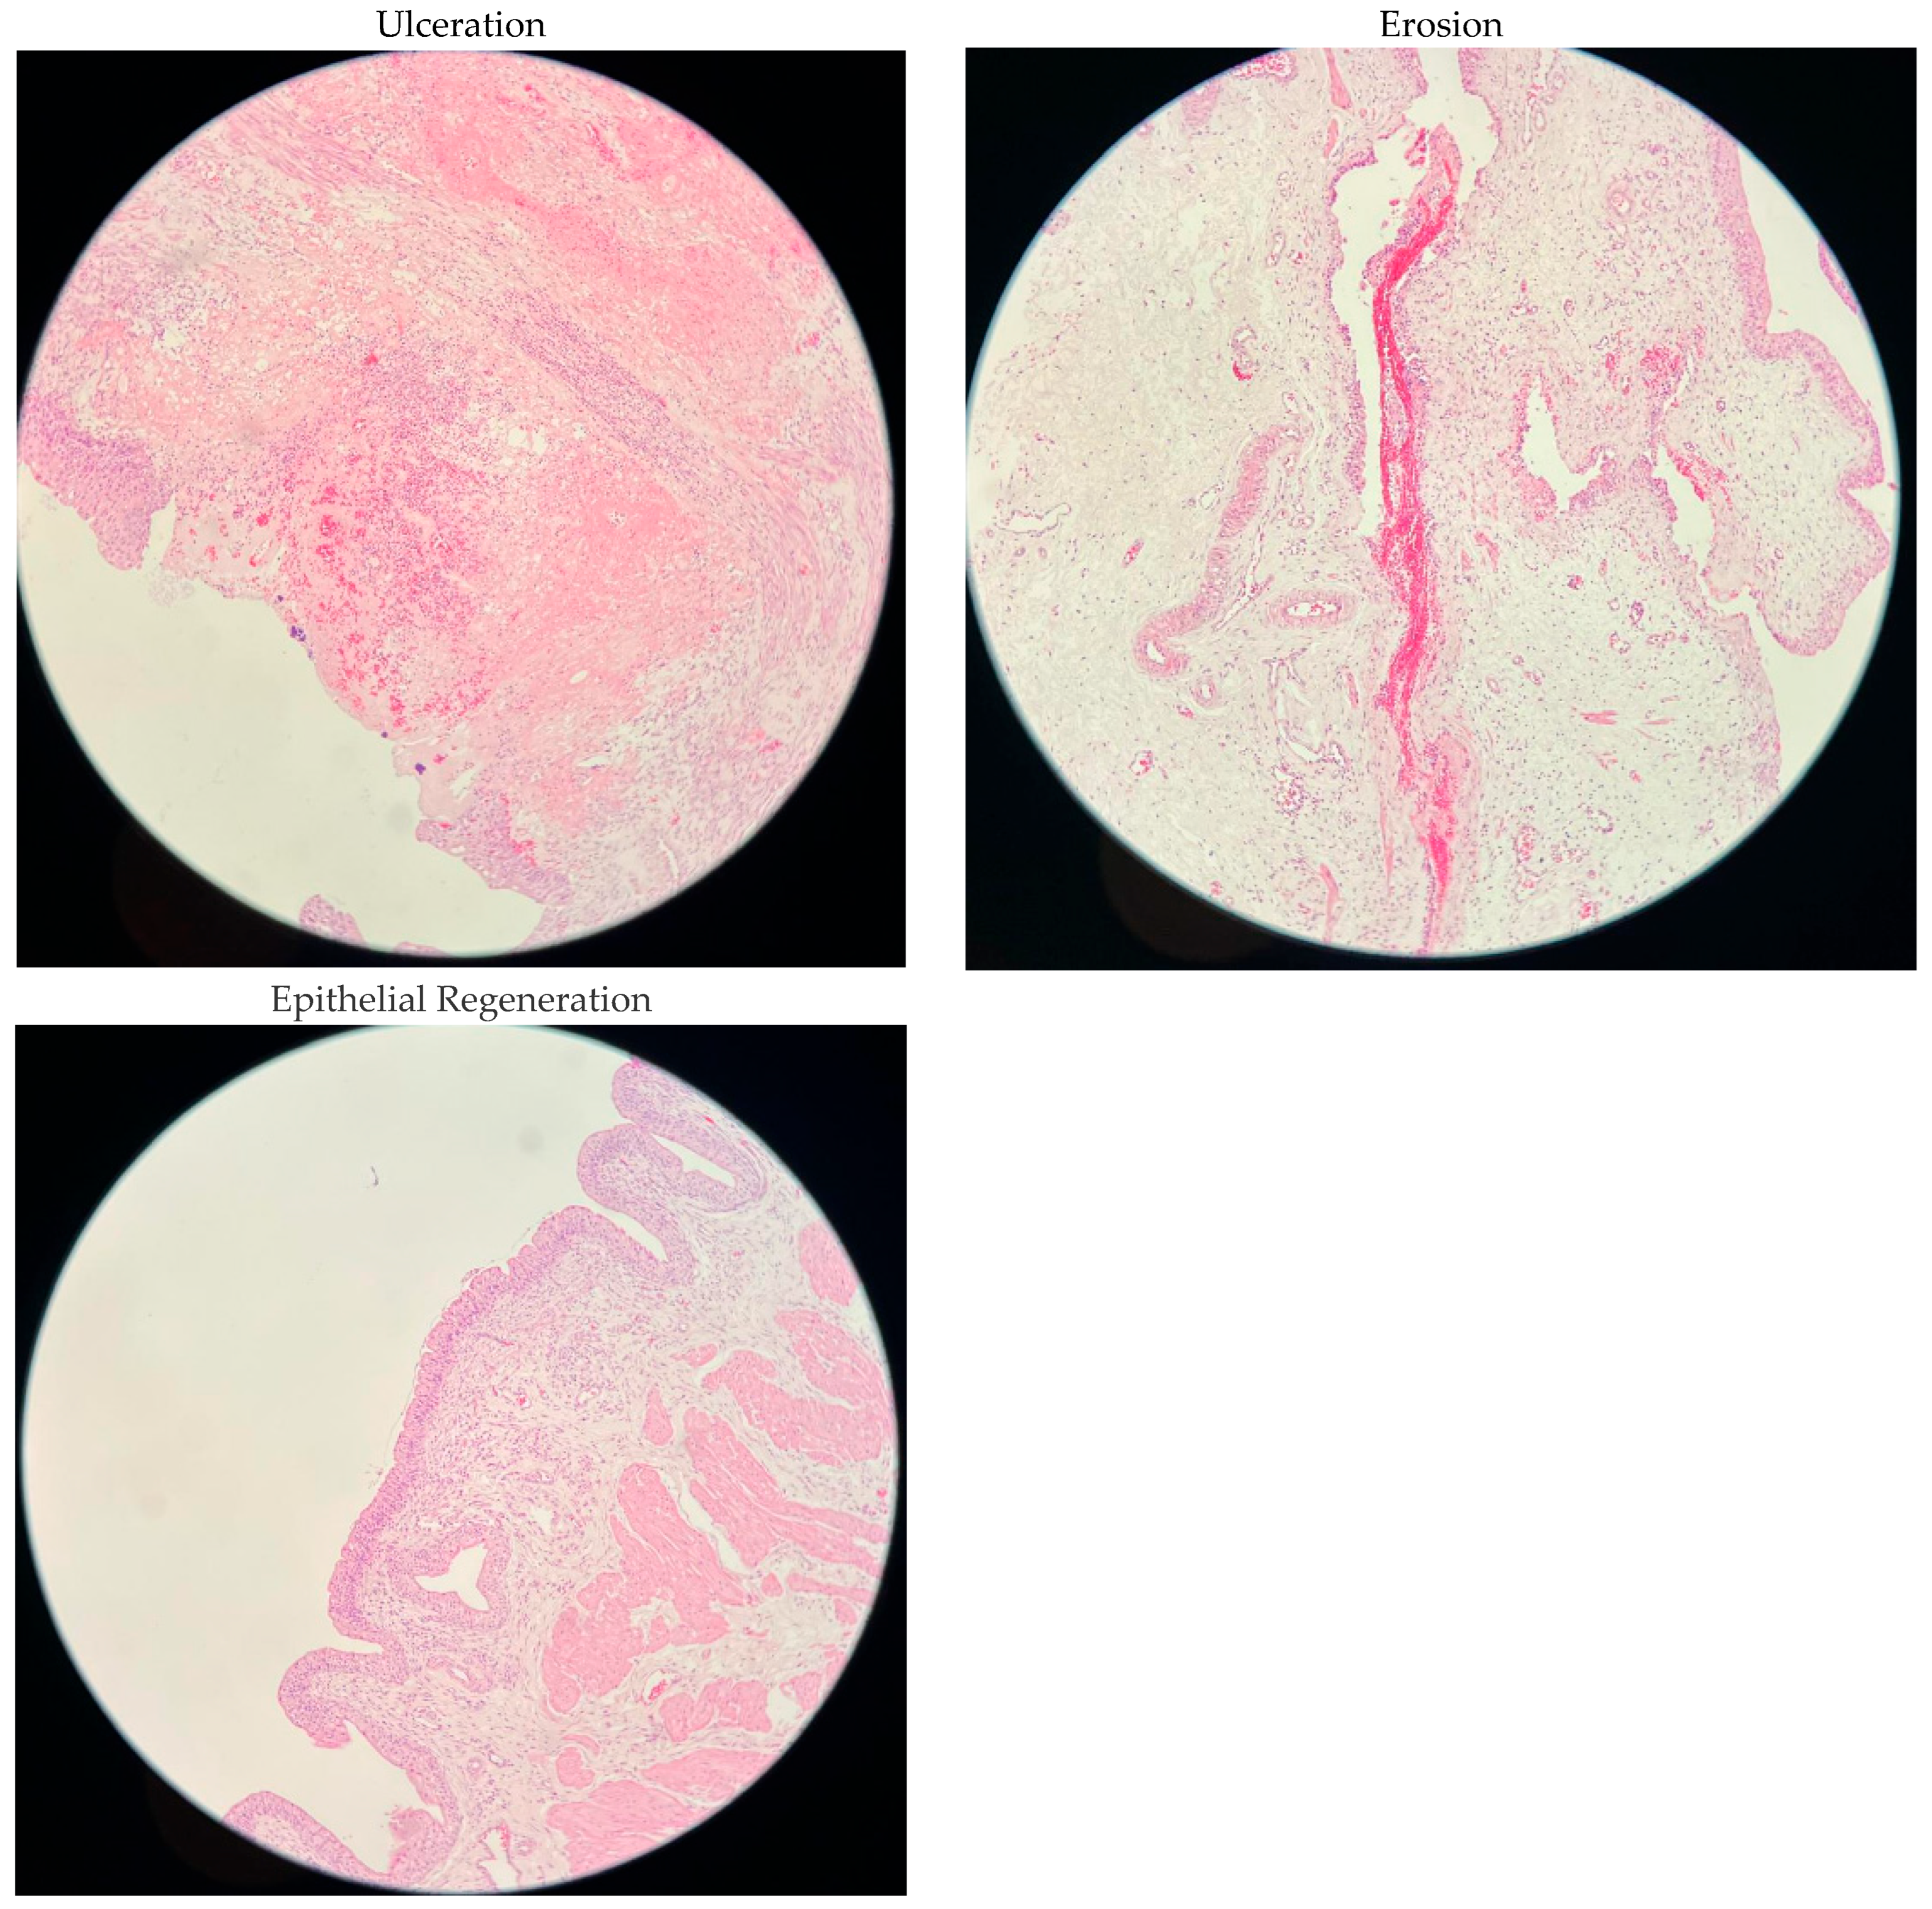

2.2. Histopathological Findings

| Ulceration | 0% | 5 (83.3) | 5 (83.3) | 5 (83.3) | 3 (50) | 0.759 |

| <25% | 1 (16.7) | 1 (16.7) | 1 (16.7) | 2 (33.3) | ||

| 25–50% | 0 (0) | 0 (0) | 0 (0) | 1 (16.7) | ||

| >50% | 0 (0) | 0 (0) | 0 (0) | 0 (0%) | ||

| Erosion | 0% | 6 (100) | 4 (66.7) | 5 (83.3) | 6 (100) | 0.573 |

| <25% | 0 (0) | 1 (16.7) | 1 (16.7) | 0 (0) | ||

| 25–50% | 0 (0) | 1 (16.7) | 0 (0) | 0 (0) | ||

| >50% | 0 (0) | 0 (0) | 0 (0) | 0 (0) | ||

| Epithelial Regeneration | 0% | 6 (100) | 4 (66.7) | 5 (83.3) | 4 (66.7) | 0.695 |

| <25% | 0 (0) | 2 (33.3) | 1 (16.7) | 1 (16.7) | ||